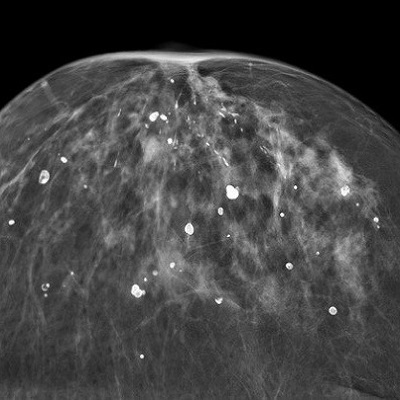

یک نوع آن بزرگنمایی می باشد. برای تهیه تصویر بزرگنمایی از یک وسیله کوچک بزرگنمایی استفاده کرده که باعث می شود پستان به منبع اشعه X  نزدیکتر و از صفحه حساس فیلم دورتر شود .

این امر باعث می شود که ناحیه مورد نظر 2 برابر بزرگتر شود . این تصویر بزرگ شده از یک ناحیه کوچک و خاص ، ارزیابی صحیح تری از حاشیه و ساختار بافتی توده یا منطقه مشکوک بدست می دهد. بزرگنمایی معمولا برای بررسی دقیق تر میکروکلسیفیکاسیون ها (رسوبات ریز کلسیمی) می باشد .